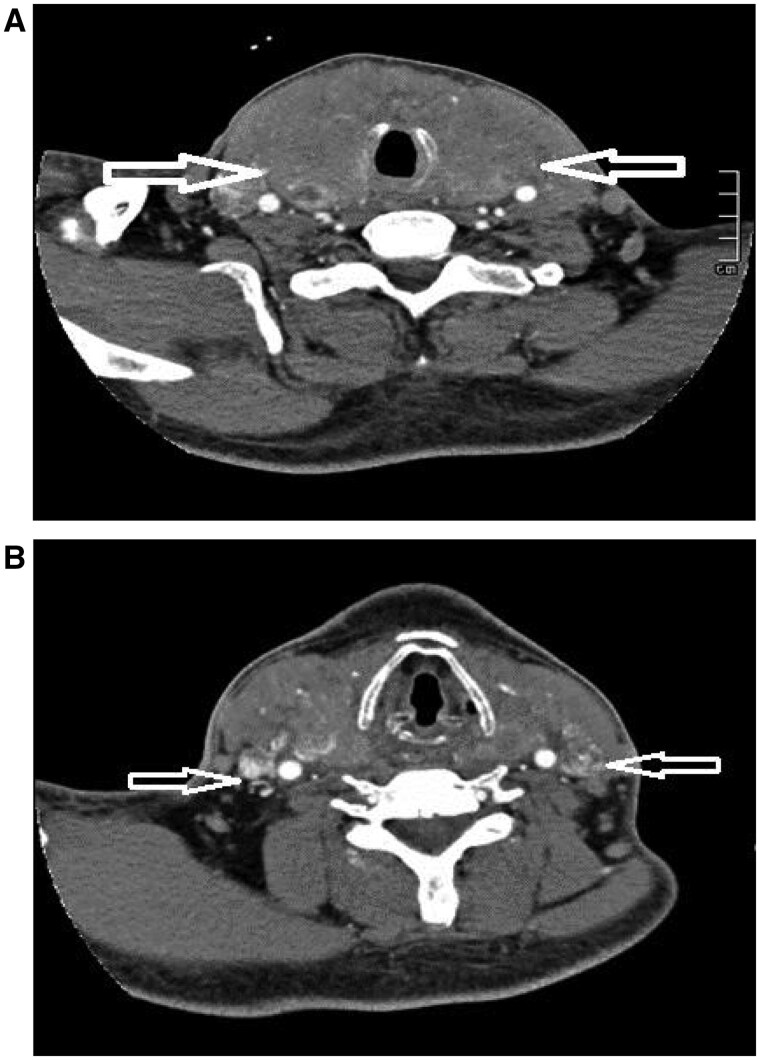

Anaplastic thyroid carcinoma (ATC) is a highly aggressive thyroid malignancy, comprising 1%-4% of thyroid cancers, with rapid local invasion and distant metastasis. We report a 57-year-old male with ATC presenting with a neck mass, hoarseness, and dysphagia. Imaging showed cancer thrombus in bilateral internal jugular veins, with a biopsy confirming ATC. This case highlights the imaging and pathological features of ATC and emphasizes the importance of ultrasound in evaluating intravascular cancer thrombus, aiding accurate diagnosis and management.

间变性甲状腺癌(ATC)是一种高度侵袭性的甲状腺恶性肿瘤,占甲状腺癌的1%-4%,具有快速的局部侵袭和远处转移。我们报告一位57岁男性ATC患者,表现为颈部肿块、声音嘶哑和吞咽困难。影像显示双侧颈内静脉癌栓,活检证实为ATC。本病例强调了ATC的影像学和病理特征,强调了超声在评估血管内癌血栓,帮助准确诊断和治疗中的重要性。